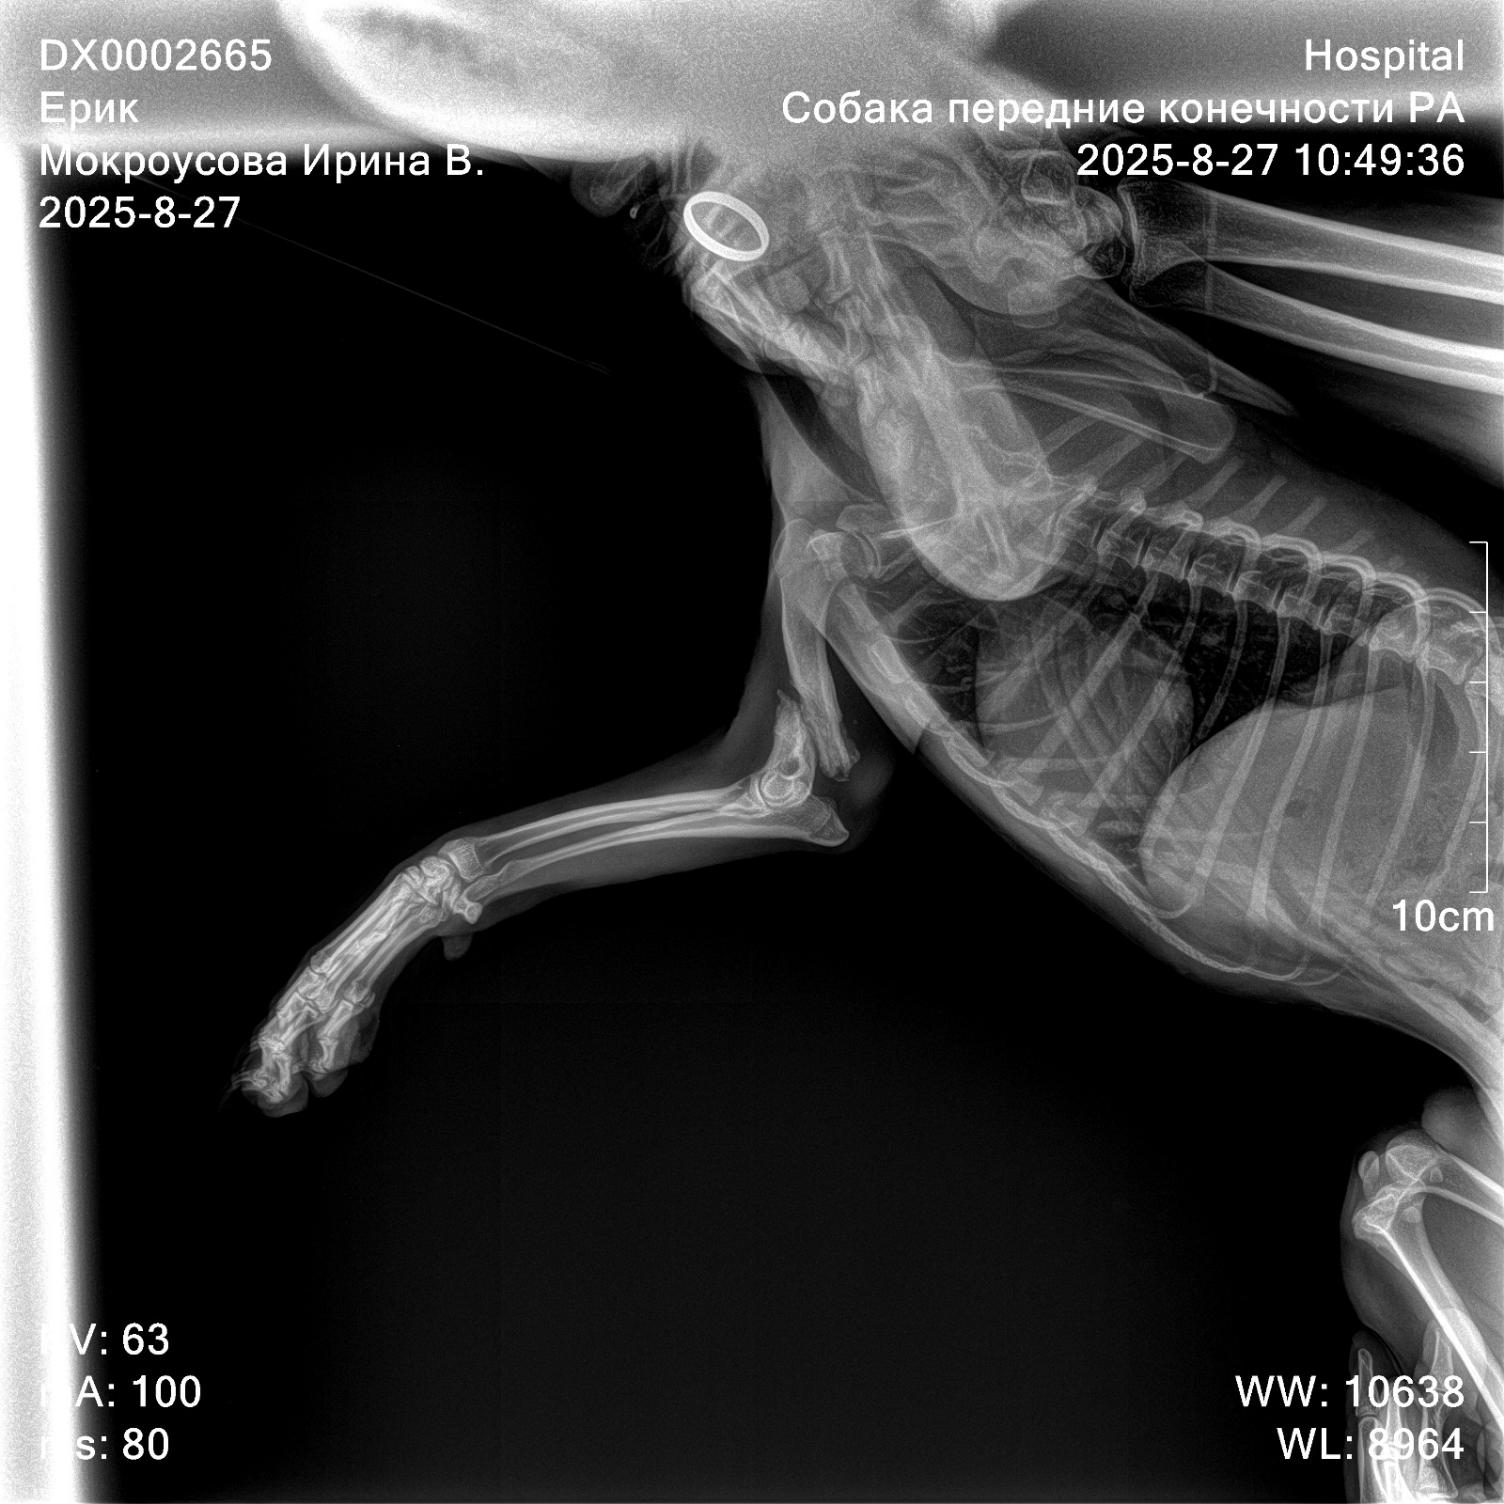

Правое плечо сломано и перелом явно не свежий. Увы, лапа не срослась, на месте перелома есть подвижность и крепитация.... Есть старый рубец.

Сегодня свозили его на рентген....

В принципе, плечо можно попробовать собрать....

Но, сначала надо очистить кости, от всего наросшего и суметь их совместить. Так как мышцы уже сократились.

Как вариант: штифт или пластина .....

Кинула рентген пока 3 хирургам.... Все считают, что операцию стоит сделать. Но лапа будет короче, чем левая.

Рентген, зубья и вся мордень